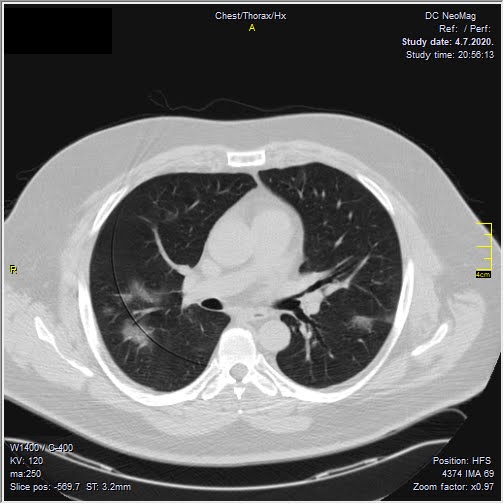

Foto: Privatna arhiva Foto: Privatna arhiva Foto: Privatna arhiva Radiolog pokazao snimak pluća i mozga 3 meseca posle kovida autor: Božica Luković Zdravlje 09. okt. 2020. 12:26 0 Podeli vest: Radiolog Aleksandar Ivković na svom blogu pruža naučni uvid u sve pojave koje je sa sobom donela pandemija koronavirusa. Rešio je da podeli kakvo je stanje jednog pacijenta tri meseca nakon što je preležao opaki virus. Podeli vest: Oglas Lekari i dalje ne znaju sa sigurnošću kakve sve posledice kovid 19 ostavlja po organizam. Postoje čak osobe koje više meseci pate od bolesti koju izaziva novi koronavirus, a mnogi prijavljuju i brojne tegobe koje ih muče i nakon negativnog testa.Niški radiolog, čije smo tekstove prenosili i ranije, ovog puta je odlučio da podeli snimke pluća i mozga svog pacijenta, koji je preležao virus pre tri meseca.Objavu sa bloga Aleksandra Ivkovića "Ljudi i ostale laži", prenosimo u celosti."Obećao sam da ću preneti kakvo je stanje pacijenata nakon kontrola. Ovde se radi o pacijentu koji je u grupi 50 - 60 godina, muškog pola, imao teži oblik kovida, nije bio na respiratoru, samo na kiseoniku.Prvi put kada sam ga pregledao bio je početak jula. Obostrana pneumonija. Foto: Aleksandar Ivković | Foto: Aleksandar Ivković Ime sam uklonio, datum se vidi, kao i ime ustanove. Ove bele fleke u plućima, koje kada se malo uveća, liče na mutno staklo, su ustvari žarišta pneumonije. Foto: Aleksandar Ivković | Foto: Aleksandar Ivković Kada bi ove bele "fleke" počele da se šire ka sredini, ka srcu, to bi značilo da se bolest širi i da se razvija citokinska oluja. Nije došlo do toga.Pacijent je došao na kontrolu nakon mesec dana. Žali se samo za zamaranje. Nema tegobe, samo želida vidi kakvo je stanje pluća. Foto: Aleksandar Ivković | Foto: Aleksandar Ivković Evidentno više nema onih zona zapaljenja. Bronhi su lako zapaljeni, mogu da se uoče mesta na kojima je bilo zapaljenje. Foto: Aleksandar Ivković | Foto: Aleksandar Ivković Ako se zagleda malo bolje prisutne su zone oštećenja alveola ali to ne spada u neki nalaz koji je zabrinjavajući.Skoro dva meseca kasnije, ponovo dolazi na pregled. Ovaj put nisu pluća u pitanju. Žali se da je konfuzan, da ne može da se seti nekih reči, da ne može da završi rečenice, da ima rupe u pamćenju.Urađen je MR pregled mozga. Foto: Aleksandar Ivković | Foto: Aleksandar Ivković Jedna ishemijska lezija, nekoliko mikroishemijskih lezija i atrofija mozga.Takav nalaz se uklapa u tegobe koje je pacijent opisao. Takođe se uklapa u ono što opisuju drugi da vide kod svojih pacijenata.Za one koji nisu shvatili još uvek - kovid 19 je opasna bolest. Od nje se umire, ostaju posledice. Nikako nije za igranje.Nikako nije ni za namerno zaražavanje, kako su neki pozivali", napisao je radiolog.***Bonus video:https://www.youtube.com/watch?v=PtivsKpglHYPratite nas i na društvenim mrežama:FacebookTwitterInstagram Srpski radiolog: 5 zabluda o asimptomatskim pacijentima Zdravlje 0 Ispovest srpskog radiologa: Golgota korone u sedam dana Zdravlje 0 Profesor Vujčić raskrinkao srpske teorije zavere o koroni Zdravlje 0 aleksandar ivković posledice koronavirusa Pratite nas na društvenim mrežama: Koje je tvoje mišljenje o ovoj temi? Učestvuj u diskusiji ili pročitaj komentare Budite prvi koji će ostaviti komentar Pošalji komentar Pročitaj komentare (0)